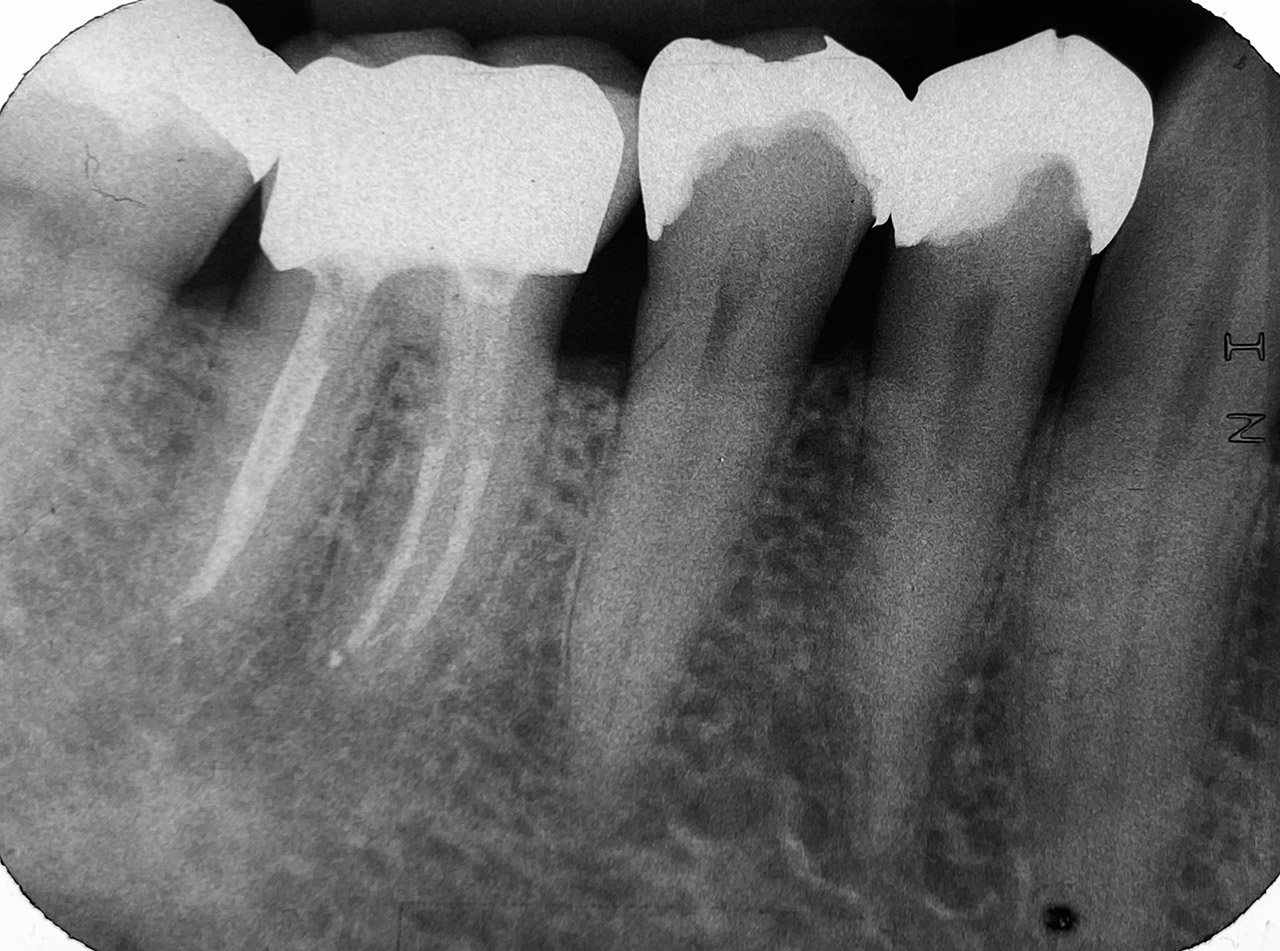

Wurzelbehandlung/Endodontie:

Massiver Paro-/Endodefekt bei den Zähnen 38&37. Extraktion von 38 (Weisheitszahn) und Wurzelbehandlung von 37 (4 Kanäle). Defekt vollständig ausgeheilt.